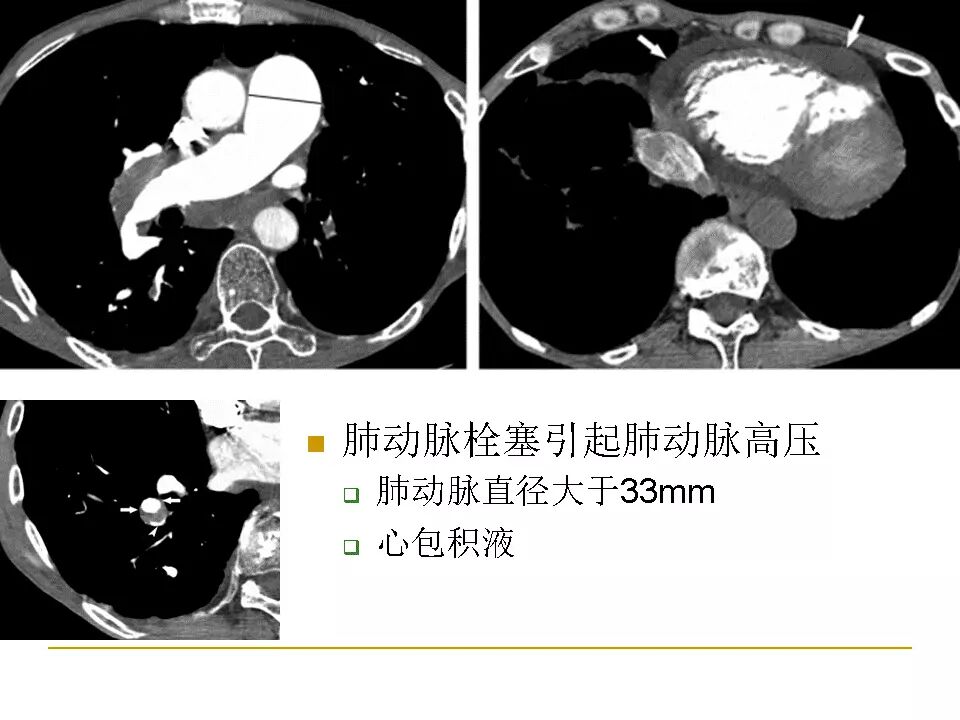

【RadioGraphics】肺动脉栓塞CTA